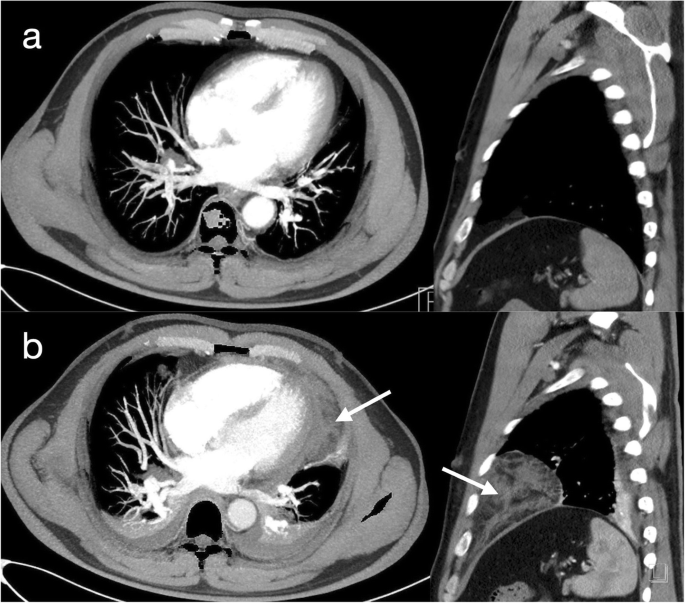

A 47-year-old man presented for inferior vena cava (IVC) filter removal, which was initially placed roughly one month prior to this hospitalization. He had a 10 pack-year history of smoking and was diagnosed with thromboangiitis obliterans for more than six months. At that time, the patient had right leg deep vein thrombosis (DVT) and bilateral segmental pulmonary embolism (PE). A nonpermanent IVC filter was placed to prevent recurrence of PE from DVT, and the DVT was treated with mechanical thrombectomy. Subsequently, the patient received long-term anticoagulation with rivaroxaban. In the present hospitalization, computed tomography pulmonary angiography (CTPA) showed that the bilateral segmental pulmonary thrombus had almost disappeared, and ultrasonography showed partial thrombus dissolution and patency of blood flow in the vein of the right lower limb. Based on the above results, it was not necessary to retain the filter. Then, interventional radiology-guided IVC filter removal was performed in the operating room. Under X-ray fluoroscopy, a snare was inserted into the right internal jugular vein, and the IVC filter was withdrawn from its hook. The procedure was uneventful. Within 30 min after the procedure, the patient developed chest pain, nausea, vomiting and presyncope. Physical examination showed a blood pressure of 70/34 mmHg, a pulse of 108 beats per minute, and a respiratory rate of 23 breaths per minute. Arterial blood gas showed a pH of 7.31, PaCO2 of 36 mmHg, PaO2 of 68 mmHg, HCO3 of 18.1 mmol/L, lactate 5.8 mmol/L and oxygen saturation of 95 %. Bedside echocardiography confirmed circumferential pericardial effusion, 1.59 cm in the largest dimension, with evidence of cardiac tamponade (Fig. 1, videos in supplementary files 1 and 2). The ideal puncture site, as defined by echocardiography, was para-apical. Pericardiocentesis was immediately performed with an 18G (1.3 × 1.06 × 65) mm needle after echocardiography localization. Confusingly, only 3 mL of bloody pericardial effusion was removed in total, and subsequently, the patient’s symptoms significantly improved except for mild subxiphoid pain. His vital signs improved approximately 3 min later, with a blood pressure of 125/95 mmHg, a pulse of 70 beats per minute, a respiratory rate of 20 breaths per minute, and an oxygen saturation of 99 %. Clotting tests indicated an INR of 1.15, an activated partial thromboplastin time of 34.7 s, and a prothrombin time of 14.5 s. Repeat echocardiography revealed that the pericardial effusion had disappeared (Fig. 1d, video in supplementary file 3). To clear up the confusion, an urgent CTPA was performed approximately 3 h after the procedure. The images showed mediastinal effusion, which had not been seen on the previous CTPA (Fig. 2a), around the left ventricle in the anterior mediastinum (Fig. 2b). Considering that the patient was asymptomatic and organ failure secondary to mediastinal effusion were not present, no intervention was suggested. He remained in the hospital for three days after the procedure. He was subsequently discharged in a stable condition, and outpatient follow-up was advised.

Echocardiography should be obtained immediately if cardiac tamponade is suspected. [7] A common sign of cardiac tamponade with significant haemodynamic compromise is collapse of the right atrium and the right ventricle. This occurs during the diastolic phase, when the intrachamber pressures are lower than the intrapericardial pressures. [8, 9] Acute tamponade generally occurs within minutes and requires urgent pericardiocentesis. Pericardiocentesis has potential risks, with major procedural complications including haemorrhagic events, cardiac perforation, pneumothorax, and arrhythmia. [10] In our case, at least 100 ml of fluid accumulated in the pericardial cavity according to the echocardiographic images; however, only 3 ml was aspirated, and the symptoms and vital signs of cardiac tamponade improved rapidly after a few minutes. These findings suggest that the tamponade had been relieved, as shown by repeat echocardiography. “Where did the effusion go?” was the question about which we were confused. Approximately 3 h after the procedure, a repeat CT scan revealed fluid accumulation in the mediastinal space.

However, mediastinal effusion due to this procedure is very uncommon. We conducted a thorough search of the literature published to date with the search terms ‘pericardiocentesis’ and ‘Mediastinal effusion or Mediastinal hematoma’ on PubMed. There are no similar published cases. In a series of 161 patients with cardiac tamponade, Maggiolini et al. [2] reported one patient whose clotting tests indicated overanticoagulation with warfarin who developed this complication within 2 days after pericardiocentesis, requiring thoracic surgery. However, this is different from our case, where our patient had no bleeding tendencies. In our case, the most likely cause was that the pericardial effusion moved into the mediastinum through the needle insertion site due to the changes in the intrapericardial pressure in response to the tamponade. When the intrapericardial pressure increases excessively due to cardiac tamponade, a bloody effusion may rapidly flow from the pericardium to the surrounding low-pressure mediastinum during the pericardiocentesis process, which led to the accumulation of an effusion in the mediastinal space.